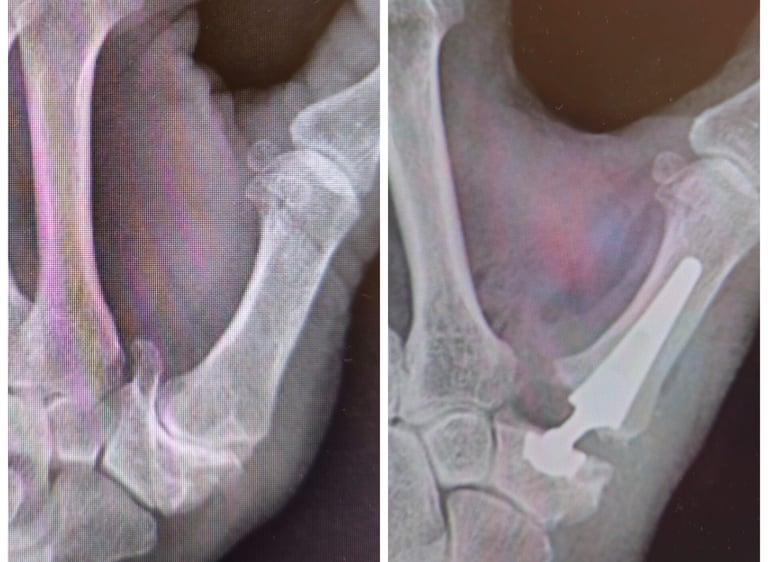

Articulación muy susceptible a algunas enfermedades como la artrosis, las fracturas de radio y cubito o las lesiones de los ligamentos.

Conoce los tratamientos más avanzados para la artrosis de la mano y cómo podemos ayudarte a mejorar tu calidad de vida